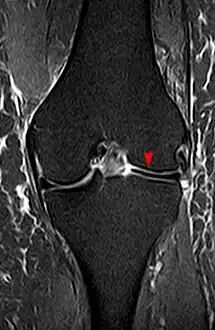

Discoid meniscus is a rare human anatomic variant that usually affects the lateral meniscus of the knee. Usually a person with this anomaly has no complaints; however, it may present as pain, swelling, or a snapping sound heard from the affected knee. Strong suggestive findings on magnetic resonance imaging includes a thickened meniscal body seen on more than two contiguous sagittal slices.

The transverse diameter of a normal meniscus is approximately 10 to 11 mm; therefore a normal meniscus body will be visible on only 2 slices of a MR with 4-5-mm sagittal slices. A discoid meniscus should be considered if more than two contiguous body segments are present. However, this method may lead to a false negative when evaluating people with the Wrisberg variant of discoid meniscus since it maintains a narrow crescent shape. Coronal and radial images of the meniscus are useful to demonstrate the extension of the aberrant meniscus into the joint as seen here. On coronal images, it is diagnosed when the horizontal measurement between the free margin and the periphery of the body is more than 1.4 cm.[1] Rarely, X-ray may show lateral joint space widening, squaring of the lateral condyle, cupping of the lateral tibial plateau and hypoplasia of the lateral tibial spine that suggest discoid meniscus.